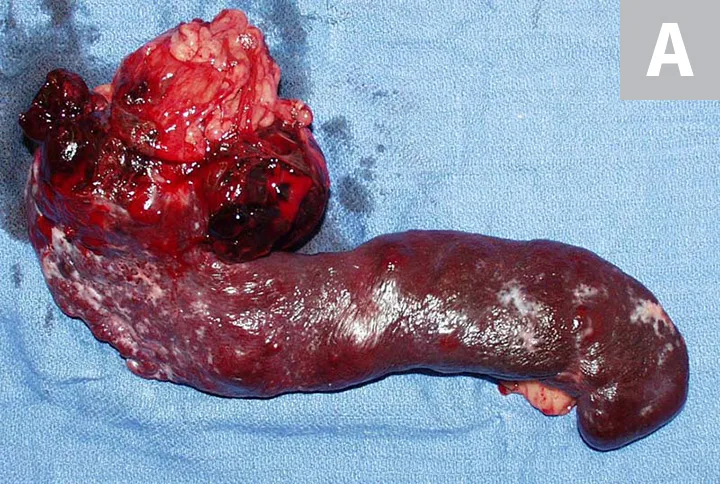

HSA can develop in any vascular organ or tissue but is most commonly found in the spleen (≈50%), right atrium and/or auricle (≈25%), and skin or SC tissue (≈15%; Figure 1).4 Most dogs diagnosed with HSA are geriatric, with a predisposition observed in German shepherd dogs, golden retrievers, and Labrador retrievers.5-7 Splenic HSA is a common splenic malignancy and is accompanied by life-threatening complications (ie, hemoabdomen and distant metastases).8-11 The mode of metastatic spread varies for patients with HSA that involves the abdominal visceral organs (eg, spleen, liver, kidneys). Regional dissemination of disease in the abdominal cavity or retroperitoneal space is enabled by the local deposition of tumor cells following primary tumor rupture, but distant metastasis requires hematogenous circulation, vascular entrapment, and successful colonization of detached tumor cells. Common metastatic sites include the liver, omentum, mesentery, and lungs.7,12 HSA also tends to metastasize to the CNS.13,14

Primary noncutaneous HSA involving the head of the spleen (A) and the right auricle (B, arrowheads). Images courtesy of Laura Garrett, DVM, DACVIM (Oncology), and Louis-Philippe de Lorimier, DVM, DACVIM (Oncology)